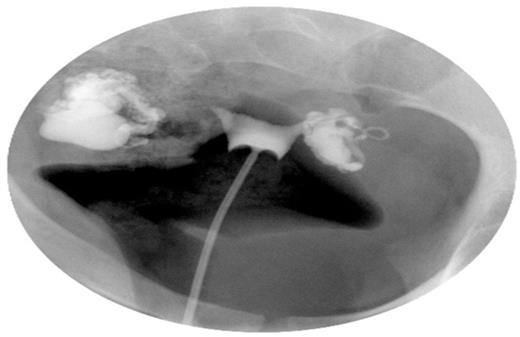

Staged combined endoscopy was performed in the operating room. Hysteroscopy revealed endometrial inflammation as evidenced by diffuse hyperemia and mucosal oedema (Figure 2A). Laparoscopic findings were significant for a right sided hydrosalpinx measuring over 2 centimeters in diameter and dense adhesions of the bowel to the left hydrosalpinx and ovary. Chromopertubation confirmed bilateral distal tubal occlusion. She underwent right salpingectomy and left tubal occlusion at the visible isthmic region via clip placement. Histopathology of the salpingectomy specimen revealed chronic inflammation. She experienced an unremarkable postoperative course and was scheduled for in vitro fertilization (IVF) treatment.

Hysteroscopic appearance of endometrial cavity immediately pre-salpingectomy (A) and six months after interruption of communication with hydrosalpinges (B). For each series, images from left to right depict right cornual, fundal and left cornual regions, respectively.

As depicted in Figure 2, the endometrial surface appears erythematous with friable and tortuous vascularity in the setting of a hydrosalpinx, and normal appearing after surgical interruption of hydrosalpingeal drainage. Subsequent IVF treatment and transfer of a single blastocyst resulted in an intrauterine pregnancy, with subsequent term delivery, indicative of functional embryo receptivity on a molecular level, although no molecular evidence is available for confirmation.